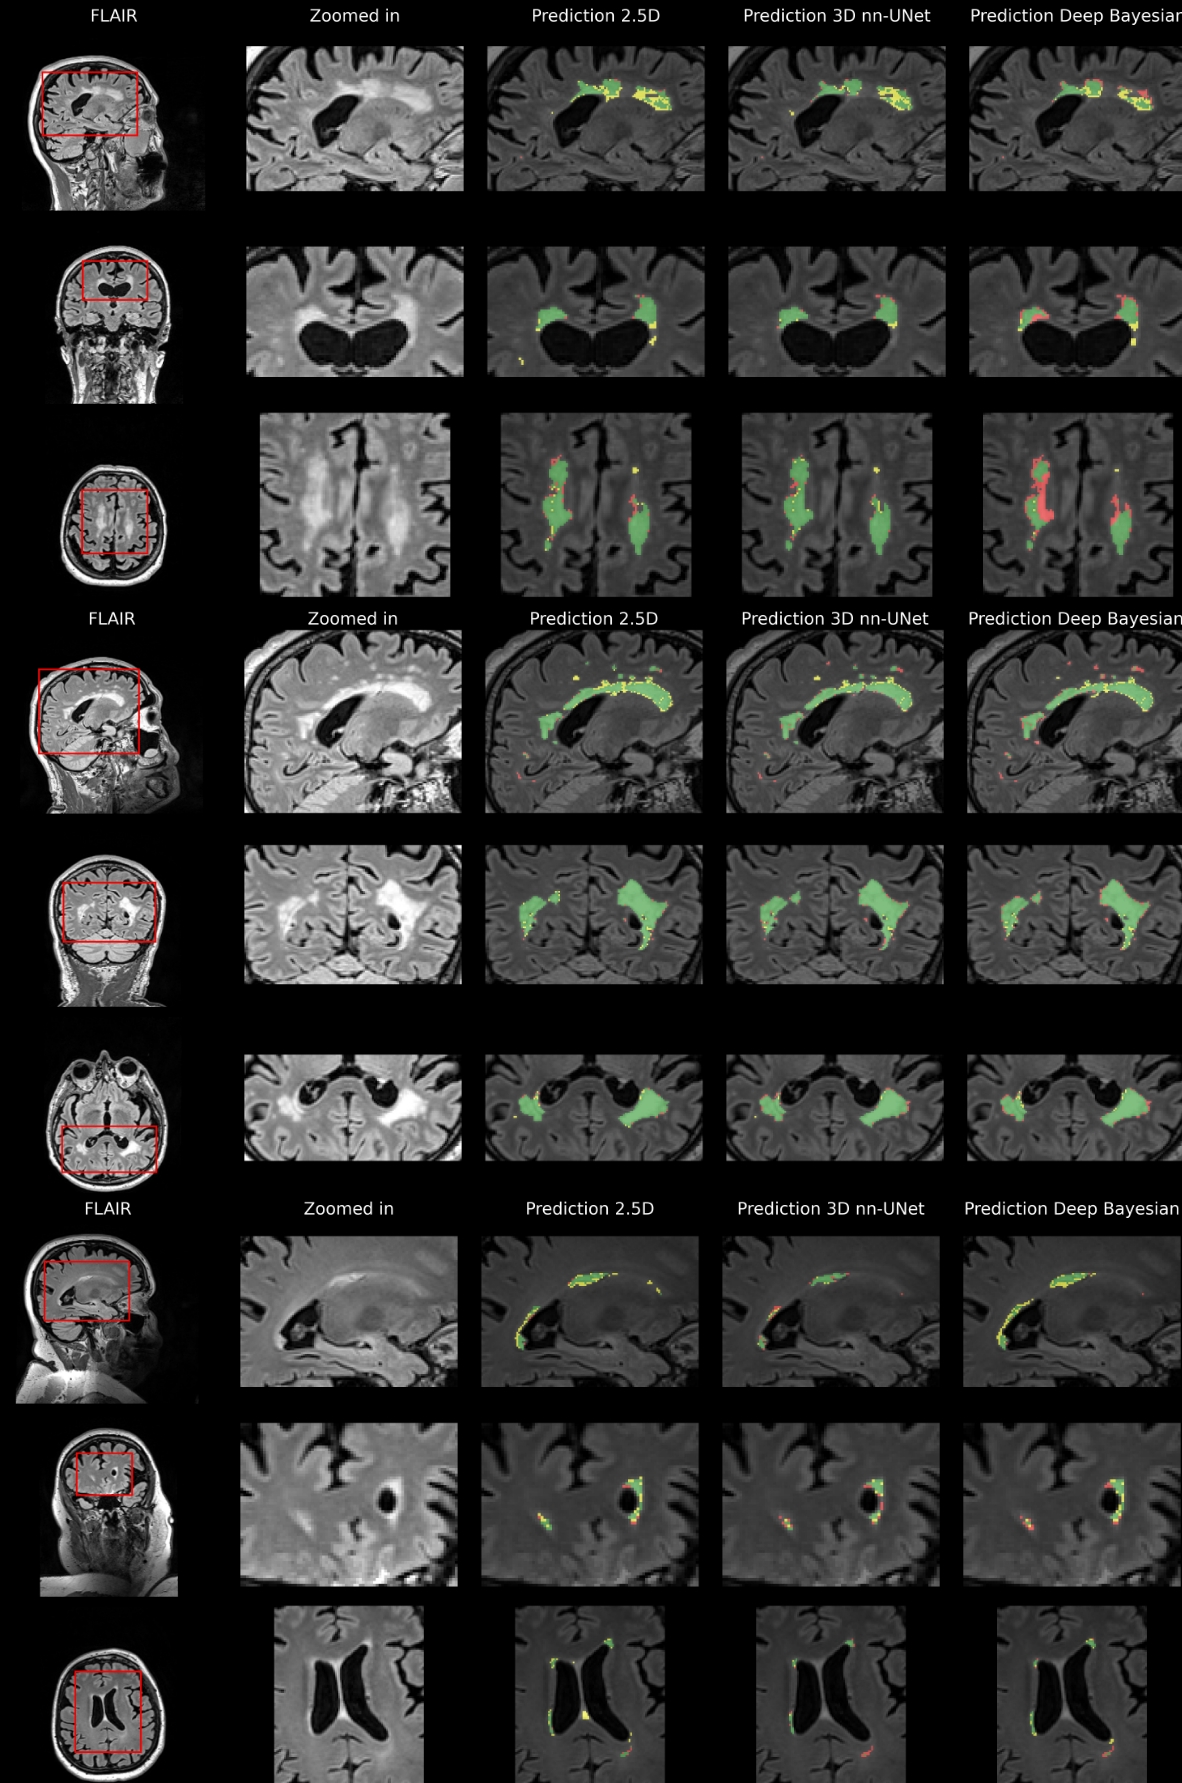

Refer to caption

Figure 9: External test data results. Predictions based on external test data overlayed on FLAIR for three participants. The first column shows three slices from each orientation for three different participants. The second column shows a zoomed-in view of an area of interest. The last columns show the segmentation results for the three different models. Green shows true positive voxels, red shows false negatives, and yellow shows false positives.